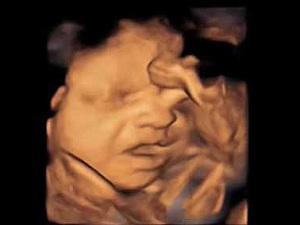

Anne karnında heceleri ayırıyorlar